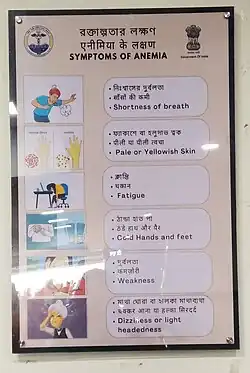

When anemia comes on slowly, the symptoms are often vague, such as tiredness, weakness, shortness of breath, headaches, and a reduced ability to exercise.[1] When anemia is acute, symptoms may include confusion, feeling like one is going to pass out, loss of consciousness, and increased thirst.[1] Anemia must be significant before a person becomes noticeably pale.[1] Additional symptoms may occur depending on the underlying cause.[1] Anemia can be temporary or long-term and can range from mild to severe.[6]

A person with anemia may not have any symptoms, depending on the underlying cause, and no symptoms may be noticed, as the anemia is initially mild, and then the symptoms become worse as the anemia worsens. A patient with anemia may report feeling tired, weak, decreased ability to concentrate, and sometimes shortness of breath on exertion.[21] These symptoms are unspecific and none of the symptoms alone or in combination show a good predictive value for the presence of anemia in non-clinical patients.[22]

Symptoms of anemia can come on quickly or slowly.[23] Early on there may be few or no symptoms.[23] If the anemia continues slowly (chronic), the body may adapt and compensate for this change. In this case, no symptoms may appear until the anemia becomes more severe.[20][24] Symptoms can include feeling tired, weak, dizziness, headaches, intolerance to physical exertion, shortness of breath, difficulty concentrating, irregular or rapid heartbeat, cold hands and feet, cold intolerance, pale or yellow skin, poor appetite, easy bruising and bleeding, and muscle weakness.[23]

Anemia that develops quickly, often, has more severe symptoms, including, feeling faint, chest pain, sweating, increased thirst, and confusion.[23][25][26][27] There may be also additional symptoms depending on the underlying cause.[1]